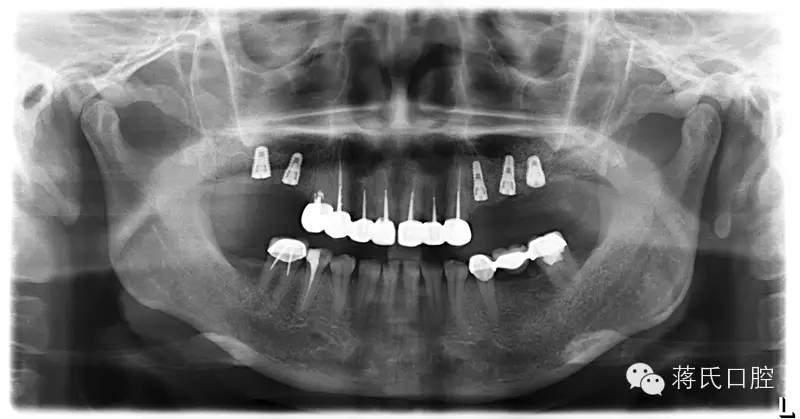

種植前X線,左側(cè)外提升右側(cè)內(nèi)提升